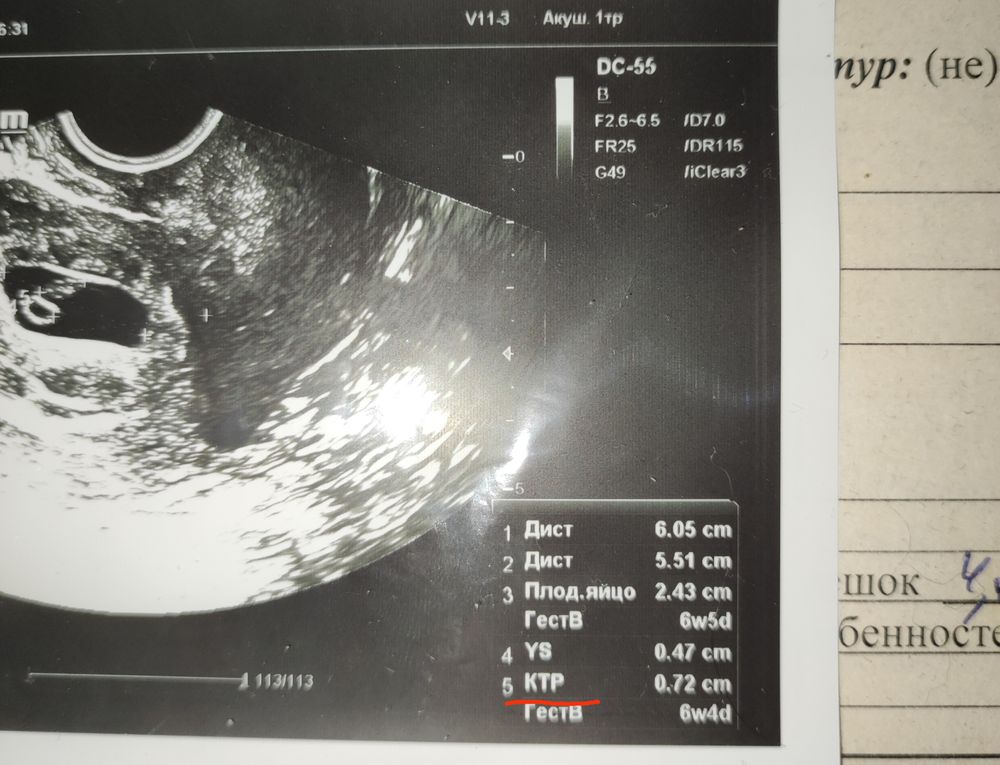

Узи на 7 нед

Всё о нашей беременностиКак говориться, до меня дошло. Прошло всего лишь 7 дней и тут меня слегка осенило: мне написали ктр 1.36мм... хм, возможно, я чего то не понимаю, но на моем сроке это очень мало. Искала в описании опечатку, но не нашла. Хорошо, что у меня есть фотография. Смотрим, крестики стоят как при измерении ктр я так предполагаю. Но постойте, если мне не изменяет мозг, что в полне обычное дело последние 2 недели, то ктр получается 1.19 см, а вот это как раз вписывается в нормы. В понедельник снова к ней на узи. Снова страшно. Как оказалось, мой Ре вполне способна довести почти до безумия. Взять фотку и спросить, что она мне написала в прошлый раз?

Ктр на снимках узи так и подписывается КТР и цифры. А то что вы видите дист 1.19 см это измерения чего то другого. Вот я добавила фото, там у вас на фотке только начало списка, а ктр должно быть ниже.